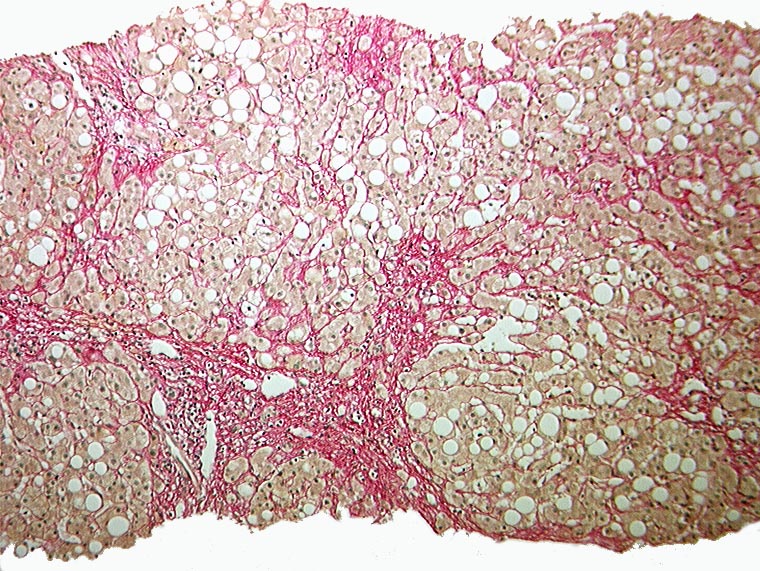

Sklerosierende Steatohepatitis, partieller zirrhotischer Umbau

Grobtropfige Verfettung. Maschendrahtfibrose. Portoportale Septenbildung.

Unvollständiger zirrhotischer Umbau mit portoportaler Septenbildung.